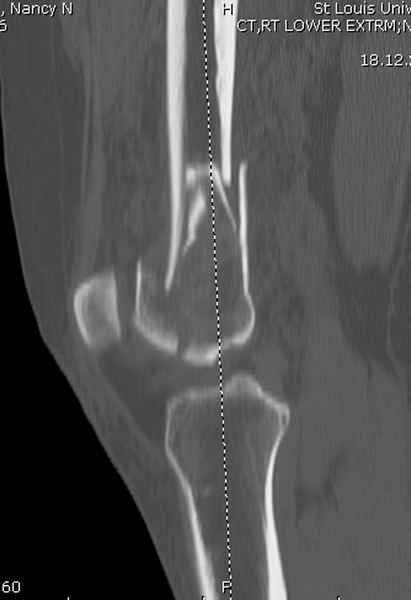

----------- следущая часть -----------

Вложение не в текстовом формате было извлечено…

Имя     : distal femur crm 5.jpg

Тип     : image/jpeg

Размер  : 17606 байтов

Описание: отсутствует

Url     : http://weborto.net:8080/pipermail/ortho/attachments/20081001/5646c87e/attachment-0015.jpg